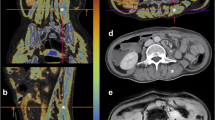

The effect of independent variables (e.g., sex, comorbidities) on the change of CT body composition parameters standardized to the varying time intervals between CT1 and CT2 is shown in Table 3 and Supplement, Table 2. The changes in CT parameters over time are schematically illustrated in Fig. 2. The DECT FF increased from 20.9% ± 12.0 to 27.0% ± 12.0 (effect size: 0.08 [0.03; 0.12], p = 0.001), while the MRA decreased from 29 HU ± 10 to 26 HU ± 11 with a proportionally smaller effect size (effect size: 0.05 [−0.08; −0.01], p = 0.009). The SMI also decreased from 35.7 ± 8.8 to 31.1 ± 7.6 cm2/m2 (effect size: −0.09 [−0.12; −0.05], p < 0.001). WC, SAT, and VAT did not change significantly. Figure 3 portrays the DECT FF and MRA at CT1 and CT2 in an exemplary 56-year-old female patient with severe pneumonia. The time interval between CT1 and CT2 in this patient was 22 days. The DECT FF increased from 3.6% at CT1 to 19.7% at CT2, while the MRA decreased from 37 to 35 HU.

Changes of DECT FF (A) and MRA (B) during immobilization of a 56-year-old female patient with pneumonia. This patient received mechanical ventilation, parenteral nutrition, and renal replacement therapy at intensive care unit, and died 3 days after CT2. The time interval between CT1 and CT2 was 22 days. A marked increase in the DECT FF and thus an increase of myosteatosis was observed. The change of the muscle radiodensity attenuation (MRA) was less pronounced, potentially due to the impact of the contrast agent on the MRA. The skeletal muscle index (not depicted) also decreased from 34.5 to 28.1 cm2/m2